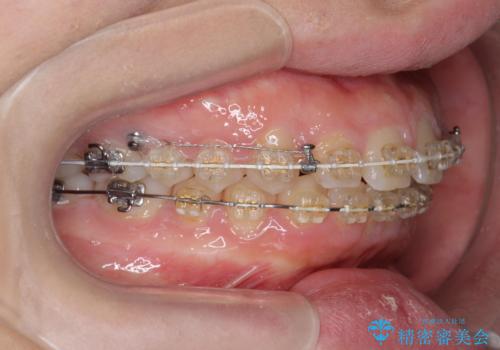

深い噛み合わせ、すきっ歯の改善 ワイヤーを用いたマルチブラケット矯正

- 噛み合わせが深く、前歯が突き出て隙間が出てきたことの改善を希望され矯正治療の相談で当院に初診来院されました。

ワイヤーを用いたマルチブラケット矯正を行うことで深い噛み合わせを改善し、前歯の隙間もなくし審美的な歯列へと治療をおこなっていきます。

深い噛み合わせの改善は前歯の圧下が必要なため、治療期間が長期化することが多いです。